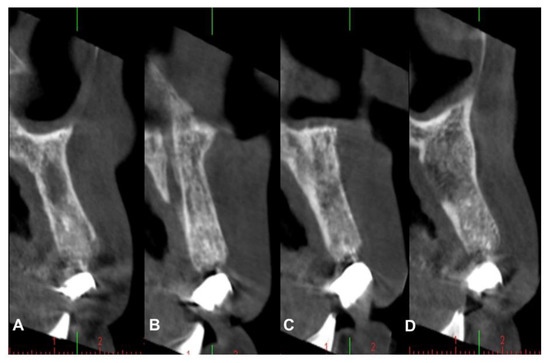

4.1. Patient No. 1

4.2. Patient No. 2

4.3. Patient No. 3

4.4. Patient No.4

4.5. Patient No.5

4.6. Patient No.6

| Patient Gender Age | Medical History of Interest [Toxic Habits] Type of Surgery | Closure by First Intention [Collagen Sponge] | I.M. | I. C. | Healing | Early Postoperative Complications | Late Postoperative Complications |

|---|---|---|---|---|---|---|---|

| 1 F 63 | NO [Tobacco: 2 cig/day] Horizontal Guided Bone Regeneration | Yes [No] | G | No | G | No | No |

| 2 M 52 | NO [-] Alveolar ridge preservation | No [Yes] | G | No | M | Graft loss and self-limited alveolitis | No |

| 3 M 61 | NO [-] Alveolar ridge preservation | Yes [No] | G | No | G | No | No osseointegration of the implant, replacement in 3 months, without problems and with good stability |

| 4 F 46 | NO [-] Alveolar ridge preservation | No [Yes] | G | No | M | Graft loss and self-limited alveolitis | No |

| 5 M 64 | NO [-] Sinus lift with lateral window | Yes [No] | G | No | G | No | No |

| 6 M 46 | NO [-] Sinus lift with lateral window | Yes [No] | G | No | G | No | No |